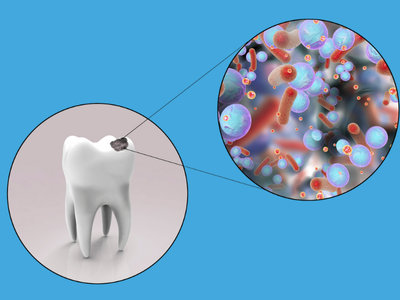

Τερηδόνα

Η πιο συχνή στοματική πάθηση, που προκαλείται από τη συγκέντρωση μικροβίων και την κατανάλωση τροφών πλούσιων σε ζάχαρη. Αντιμετωπίζεται με σφραγίσματα και, σε πιο προχωρημένα στάδια, με θεραπείες αποκατάστασης.